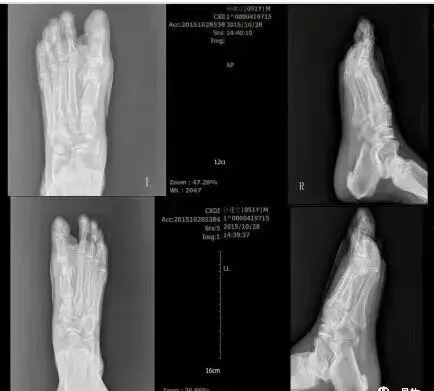

术前术后X光片对比图

术后X光片参考